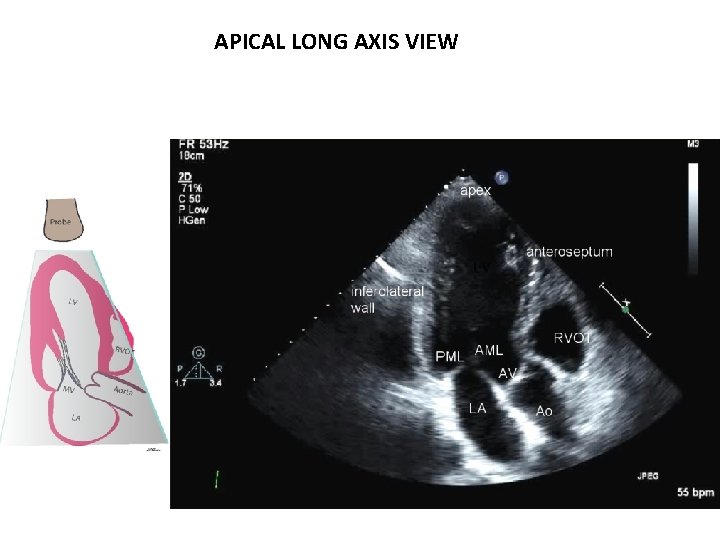

APICAL LONG AXIS VIEW